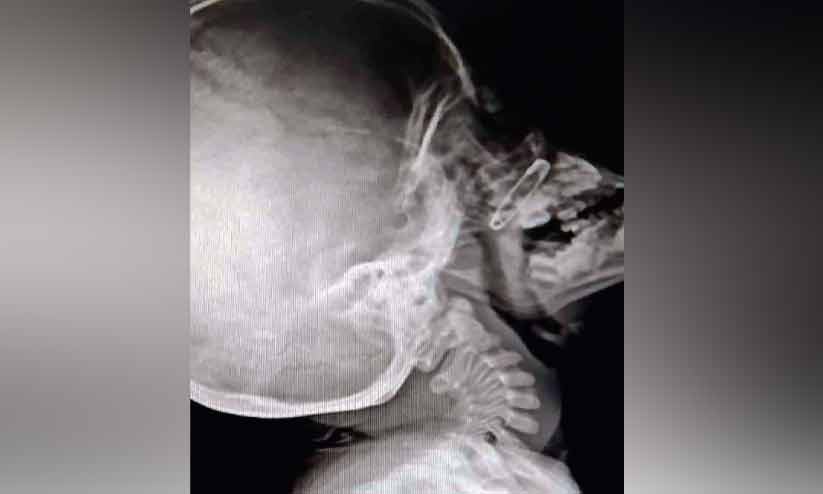

text_fieldsഅഞ്ചുവയസ്സുകാരന്റെ മൂക്കിൽ എട്ടുമാസം മുമ്പ് കുടുങ്ങിയ പിൻ. എക്സ്റേ ചിത്രം

എന്നാൽ, വിശദപരിശോധനയിൽ കുട്ടിയുടെ മൂക്കിനകത്ത് പിൻ ഉണ്ടെന്ന് കണ്ടെത്തി. എട്ടുമാസത്തോളം മൂക്കിനകത്ത് ഇരുന്നതുകാരണം കോശങ്ങൾ വളർന്ന് പിൻ ശരീരത്തിനുള്ളിൽ അകപ്പെട്ട അവസ്ഥയിൽ ആയിരുന്നെന്ന് എക്സ്റേയിൽ വ്യക്തമായി. പിൻ കണ്ടെത്തിയിരുന്നില്ലെങ്കിൽ ഭാവിയിൽ കുട്ടിയിൽ ആരോഗ്യ പ്രശ്നങ്ങൾക്ക് ഇടയാക്കുമായിരുന്നെന്ന് ഡോക്ടർമാർ ചൂണ്ടിക്കാട്ടി.